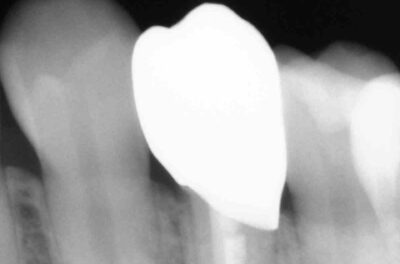

Специализация: терапия(эндодонтия), ортопедия, имплантология.